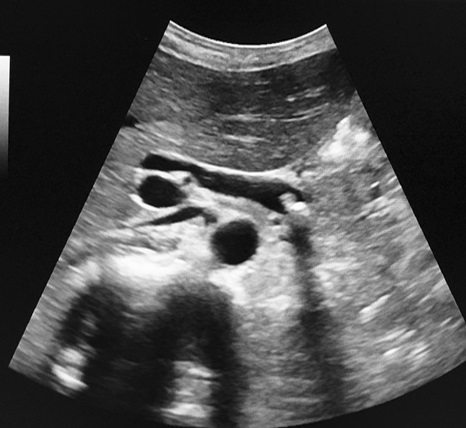

Image echographique d'une

calcul de voie biliaire principale avec image du

calcule et de canal choledocque en dilate ;

20% de calcul choledociennes est hyperdensite (

hyperechogene ) .

Coupe longitudinal du canal |